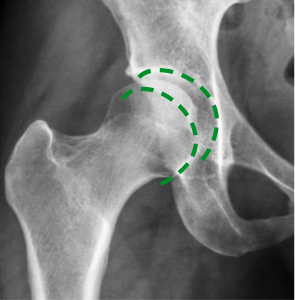

Na zdjęciu po lewo (wykonanym przed kuracją) widać niedobór mazi stawowej, który powoduje ścieranie się kości. Na zdjęciu po prawej stronie dzięki kuracji kości poruszają się płynnie i bezboleśnie. Struktura mazi stawowej się odbudowała – odzyskała właściwości poślizgowe.

Prof. Zygler udowodnił (o czym świadczą zdjęcia rentgenowskie i USG), że jego formuła antyartretyczna wpływa na regenerację stawu na trzech głównych płaszczyznach: